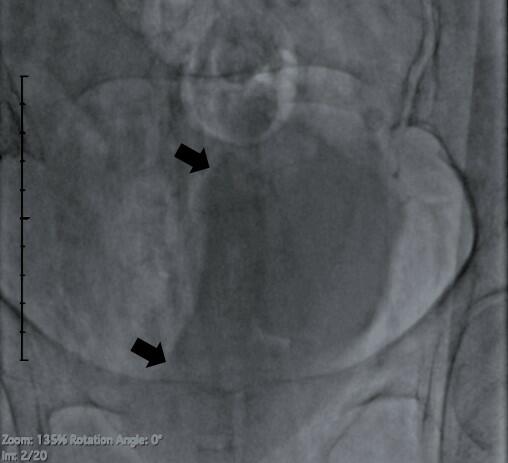

Bladder Indentation Sign: A Stitch in Time Can Save Nine

Video Supplement to "Bladder Indentation Sign: A Stitch in Time Can Save Nine" (November 2023 Clinical Image).